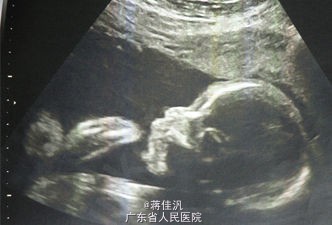

T:36.8℃,BP:170/115mmHg。 专科检查:宫高29cm,腹围86cm,胎位LOA,胎心150/min,未触及敏感宫缩。双下肢膝关节以下非凹陷性水肿。 辅助检查:血常规:WBC 4.6*10^9/L,RBC 4.28*10^12/L,HGB 146g/L,PLT 162*10^9/L,LYM% 0.288,GRAN% 0.682。CRP、PCT正常。子宫双附件B超示:宫内妊娠单活胎,相当于孕33周。胎监9分。尿常规示:尿蛋白(3+)。